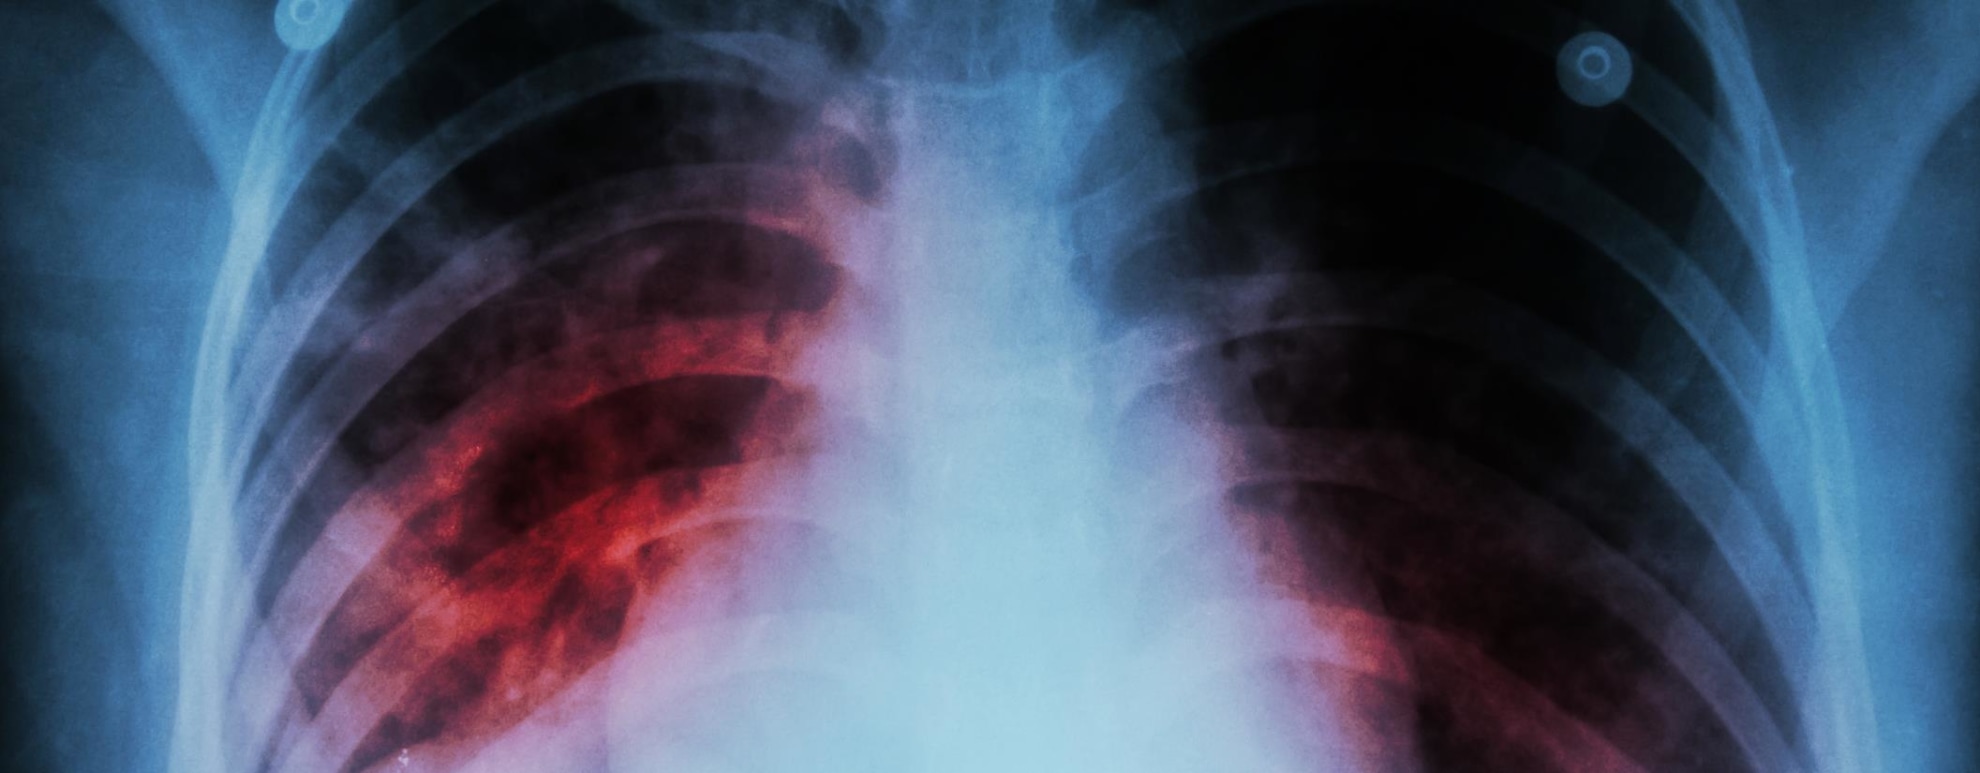

In 2016, over one and a half million people died each from Tuberculosis, diarrhoea and lower respiratory infections. These aren’t just one year problems. out these diseases as they are communicable, just like the virus. These are every year problems yet I don’t recall the lockdowns for tuberculosis or not being able to go to the pub because of diarrhoea.

Add to this list, all the other causes of death in excess of these numbers: Ischaemic heart disease, over 9 million; stroke, over 5 million, Chronic obstructive pulmonary disease, over 3 million. There are others. People in developing countries must wonder what is going on in the developed nations.